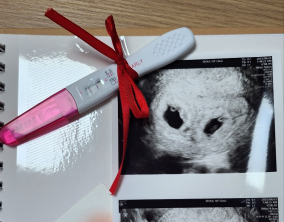

기대보다 먼저 찾아온 선물 같은 순간

이경훈 원장님께서 친절하고 꼼꼼하게 신경 써 주셨고, 간호사 분들께서도 하나하나 자세히 설명해 주시며 공감해 주셔서 치료 과정이 훨씬 편안하게 느껴졌습니다. 의료진 모두…